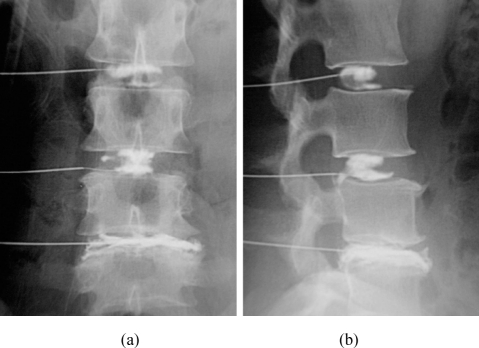

3. Transpedicular approach: A curved introducer is advanced through the pedicle into the vertebral body under fluoroscopic guidance

Transpedicular Approach:

• The introducer needle (typically 8G) enters at the superior-lateral aspect of the pedicle and advances toward the inferior-medial aspect

• Frequent alternating between true AP and true lateral imaging is essential to avoid breaching the pedicle cortex

• Goal: reach the posterior vertebral body in the lateral view before reaching the medial or inferior pedicle walls in the AP view